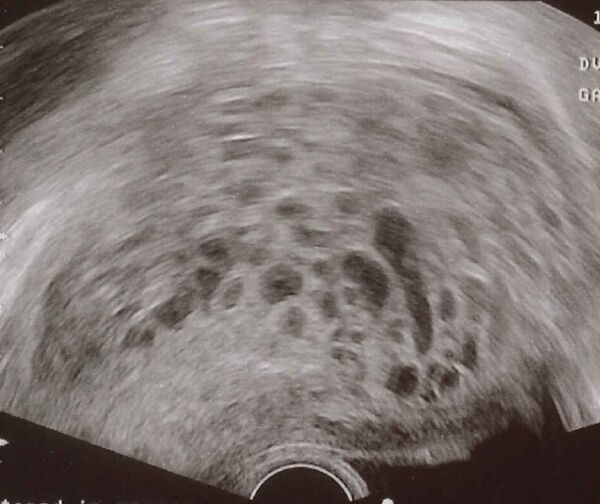

Диагностика

Диагноз пузырного заноса устанавливается при ультразвуковом исследовании[3]. Вместо нормальной структуры плодного яйца обнаруживается пёстрая картина, получившая название «снежной бури». В яичниках определяются лютеиновые кисты. При исследовании гормонов отмечается высокий уровень хорионического гонадотропина (ХГЧ), иногда многократно превышающий уровень при нормальной беременности.